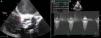

El ecocardiograma posvalvuloplastia reportó área valvular de 0,6 cm2, gradientes sistólicos aórtico máximo de 66mm Hg y medio de 35mm Hg, y velocidad del flujo transvalvular aórtico en el pico de la sístole de 4 m/s3 (fig. 3).

A) Imagen de válvula aórtica por ecocardiografía transesofágica, eje corto, obtenida después del procedimiento de valvuloplastia con balón. Se nota calcificación extensa de las valvas y apertura valvular reducida. B) Gradiente sistólico aórtico máximo por Doppler continuo=66mm Hg, medio=35mm Hg.

Vao: válvula aórtica.